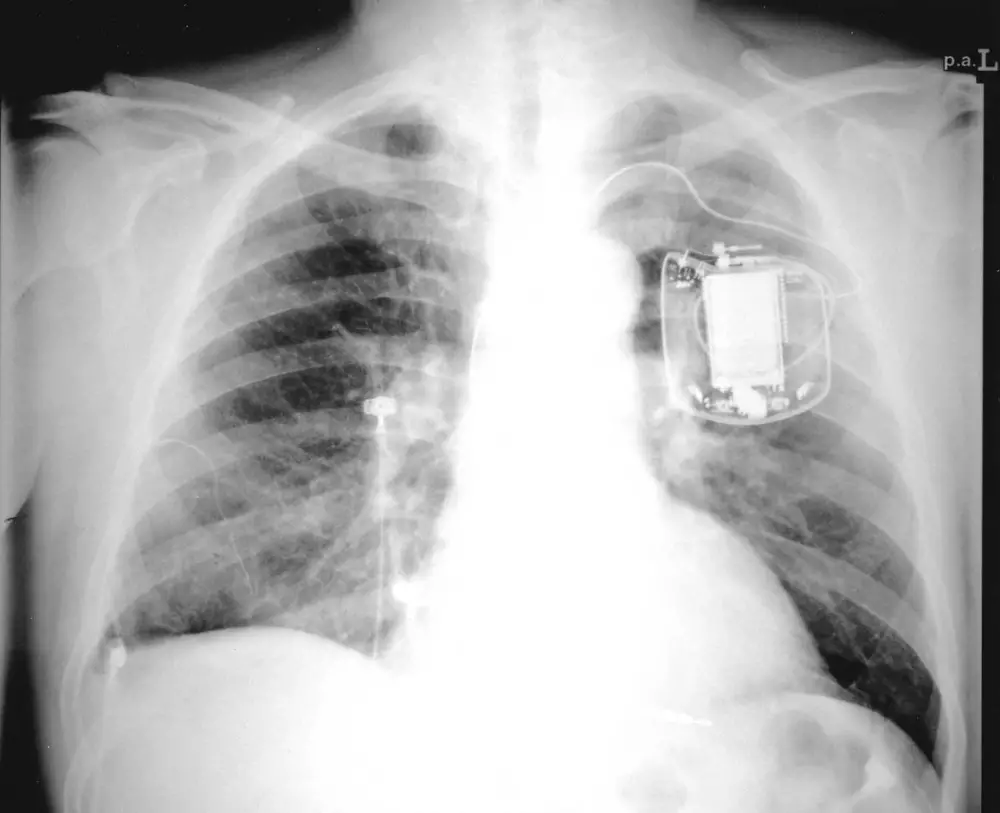

Казахстанские врачи проникли в сердце пациента через Интернет, сообщает Tengrinews.kz. Специалисты Республиканского научного центра неотложной медицинской помощи Национального медицинского холдинга провели уникальную операцию. Больному со сложным нарушением ритма сердца врачи имплантировали кардиостимулятор с функцией дистанционного мониторинга. Как сообщила 27 апреля 2011 года пресс-служба Национального медицинского холдинга, имплантированный прибор обладает функцией "Home Monitoring", суть которой заключается в возможности следить за состоянием пациента на расстоянии посредством Интернета, что облегчает взаимодействие между пациентом и врачом. Операцию проводил врач-аритмолог Адиль Баимбетов, специализирующийся на интервенционном лечении нарушений ритма сердца. В сообщении пресс-службы отмечается, что в 2011 году в Республиканском научном центре неотложной медицинской помощи планируется внедрение новых методов интервенционного лечения нарушений ритма сердца, таких как криоаблация, радиочастотная аблация очагов аритмий в сердце, навигационные системы в диагностике и лечении тахиаритмий. На сегодня в центре успешно проведены более 60 имплантаций различных антиаритмических и кардиоресинхронизирующих устройств.